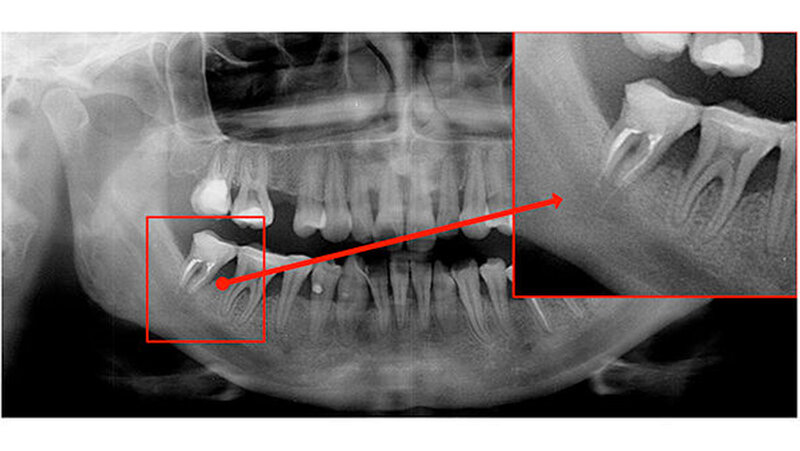

Der Zahn 47 stellte sich parodontal geschädigt und 1-gradig gelockert dar. Das Orthopantomogramm (OPTG) und der anschließend angefertigte Zahnfilm (Abbildungen 2 und 3) zeigten am Zahn 47 apikal weit überextrudiertes Wurzelfüllmaterial. Die Patientin wurde aufgrund der klinischen und der röntgenologischen Befunde sofort an die Klinik und Poliklinik für Mund-, Kiefer- und Gesichtschirurgie überwiesen.

Die dreidimensionale Darstellung des Unterkiefers rechts mittels digitaler Volumentomografie (DVT, Abbildung 4) vervollständigte den Nachweis von röntgenopakem Material im Bereich der Wurzelspitzen des Zahnes 47 mit direktem Kontakt zum Nervus alveolaris inferior. Die Rücksprache mit dem ausländischen Behandler ergab die Information, dass es sich bei dem Füllmaterial um Guttapercha zusammen mit einem paraformaldehydhaltigen Zement handelte.